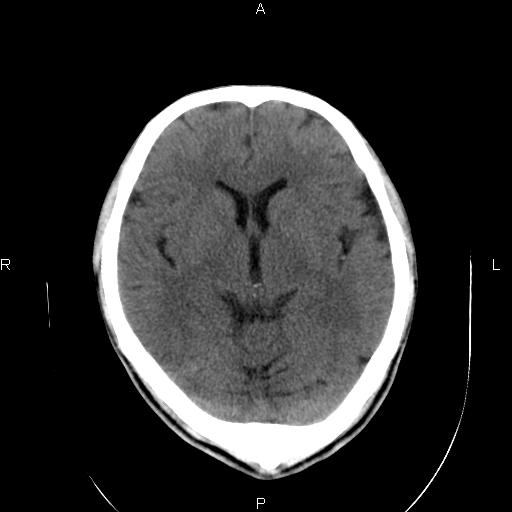

男性,40岁,反复头痛,视物旋转一月余,无呕吐,pe未见明确异常。

我的问题是上矢状窦高密度怎么解释?请各位专家不吝指教,谢谢!

可结合增强或mrv检查除外上矢状窦血栓。

未见明显异常,必要时mri

颅脑平扫未见异常,必要时mri检查。

颅脑ct轴位平扫颅内未见明确异常;建议必要时行mri检查。